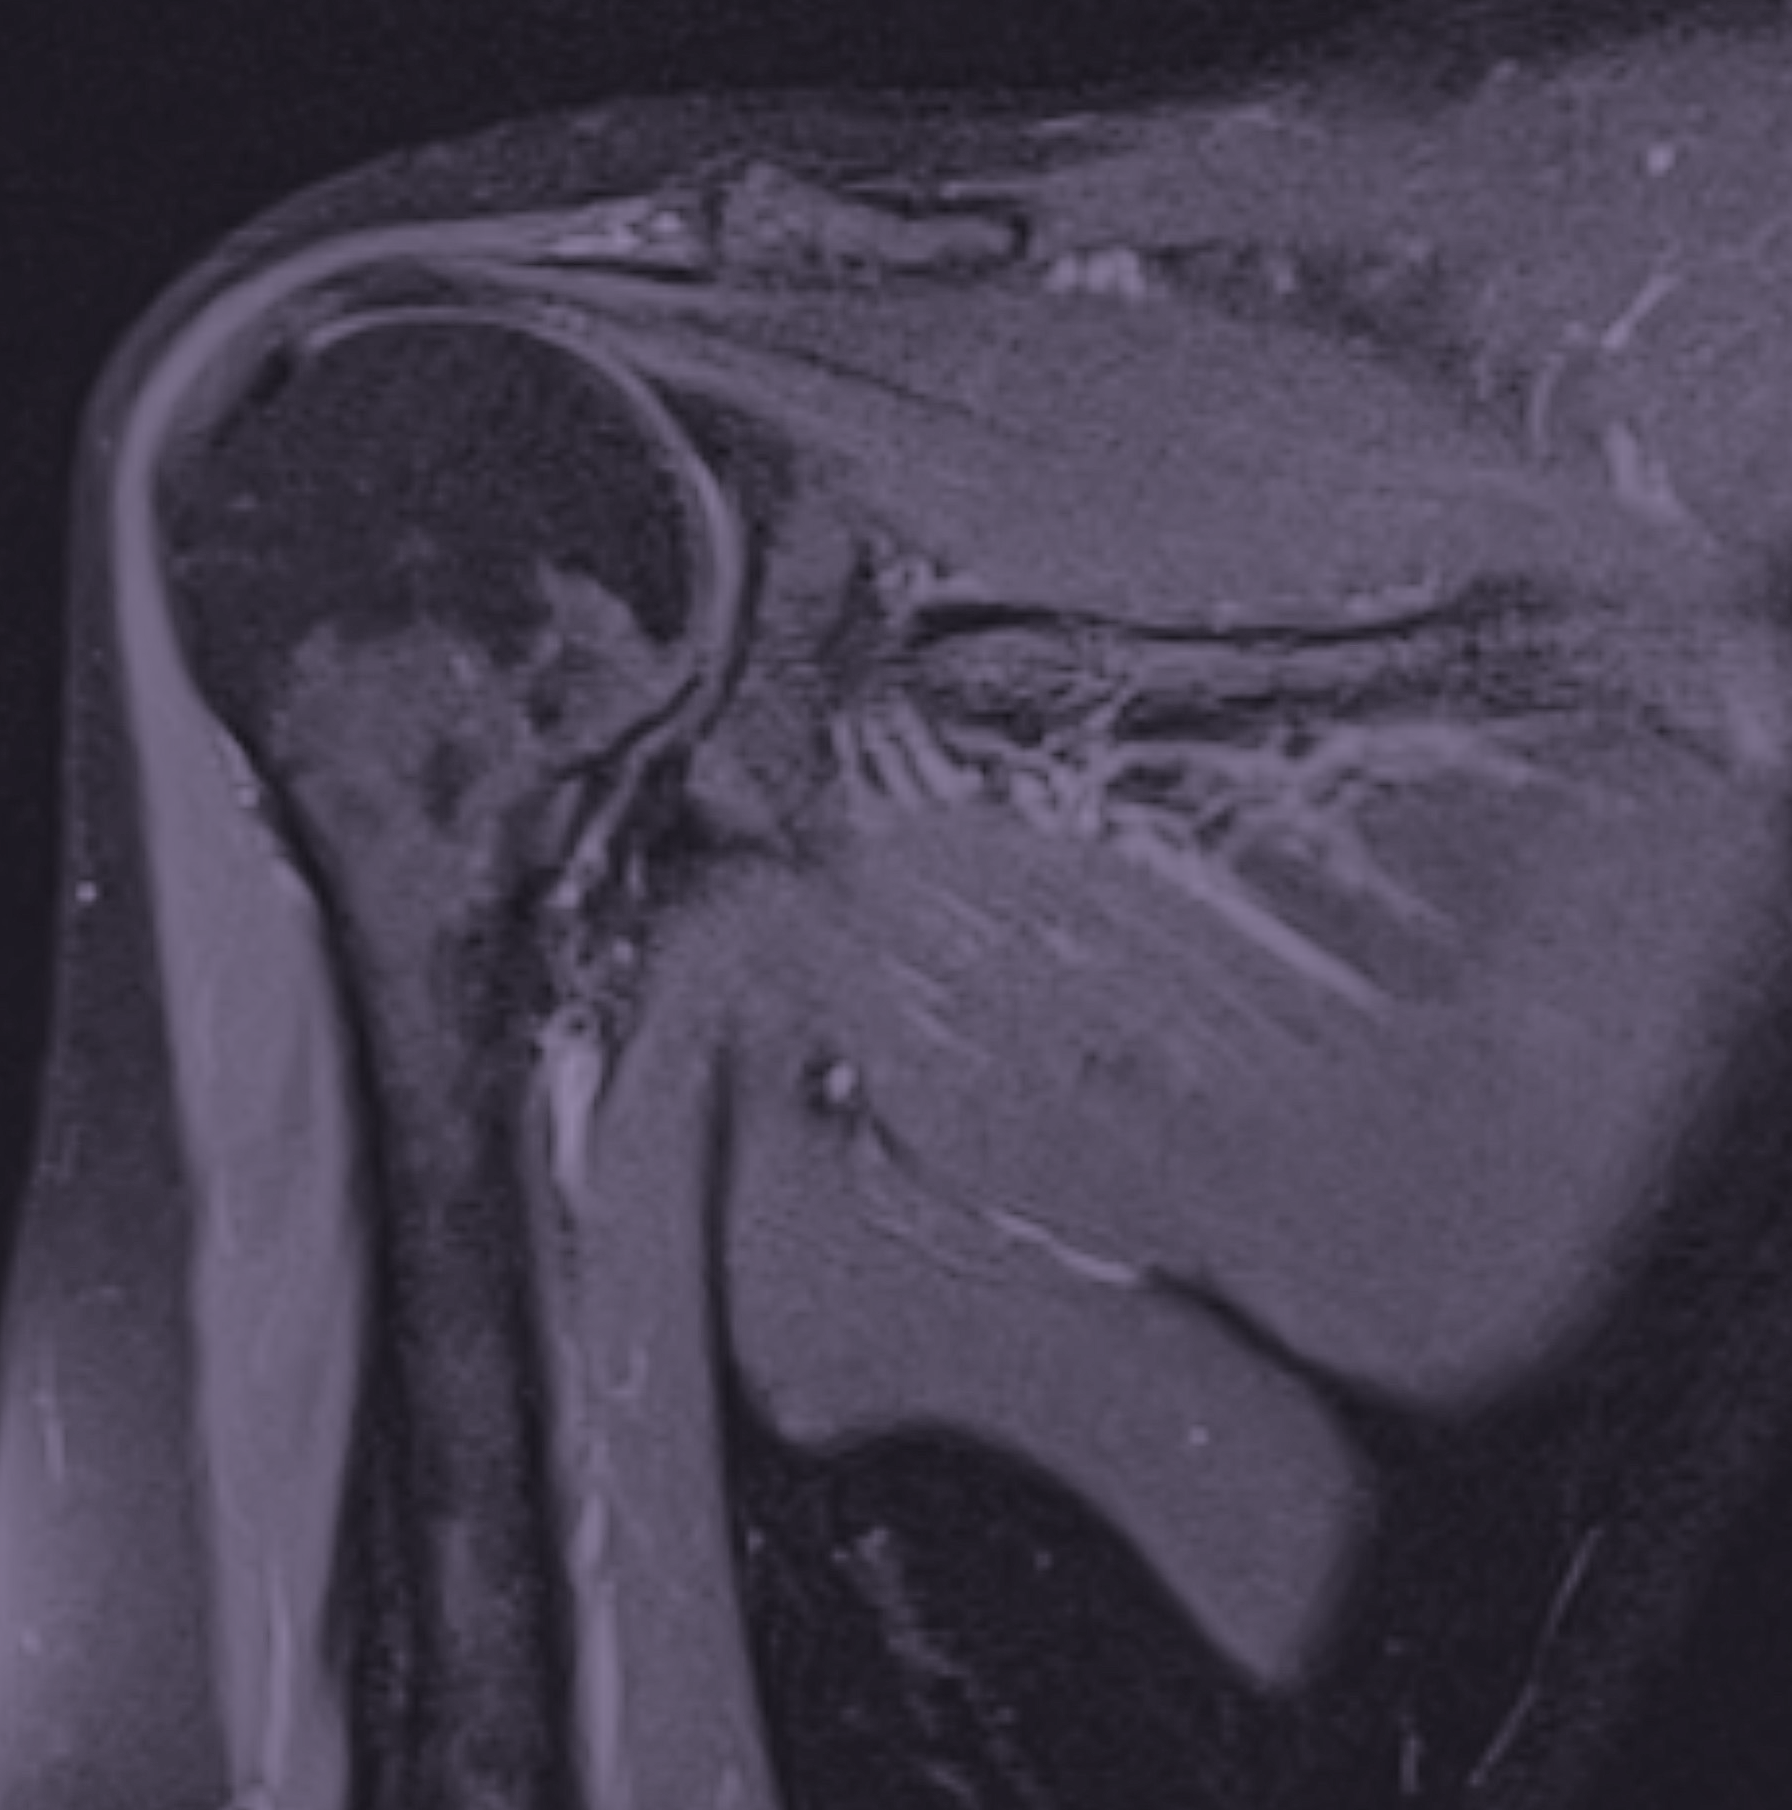

Vid en MR-undersökning av axeln undersöks de strukturer som vanligtvis ligger bakom smärta och nedsatt funktion. Eftersom många axelbesvär sitter i mjukdelarna som senor, muskler och brosk är MR en relativt träffsäkra metoderna för att identifiera orsaken.

Till skillnad från vanlig slätröntgen som främst visar skelett, kan MR tydligt visualisera rotatorkuffen, ledens brosk och andra viktiga strukturer i axeln. Det gör undersökningen särskilt värdefull vid exempelvis långvarig smärta, misstänkta senskador eller när rörligheten i axeln är nedsatt utan tydlig förklaring.

En MR av axeln ger en detaljerad bild av både ledstrukturer och mjukdelar, vilket gör det möjligt att identifiera förändringar som inte syns med andra bilddiagnostiska metoder. Ofta är det en kombination av flera fynd – snarare än en enskild skada – som tillsammans förklarar symtomen.

MR av axeln